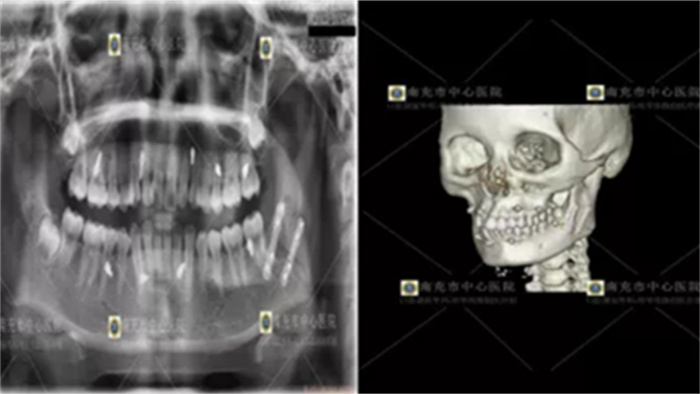

![]() |

| 手术前X片 |

口腔颌面外科微创亚专业组组长明华伟副主任医师结合患者的病史体征及辅助检查,诊断为左下颌角骨折,需要手术治疗。结合小颜的诉求,经科室讨论,决定为小颜实施“经口内切口入路、腔镜辅助下左下颌角骨折切开复位内固定术”。